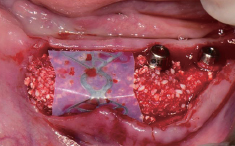

#45 협측 골이식

Wifi-Mesh 준비 및 다듬기

#45 & #46 골 결손 부위에

Wifi-Mesh 위치시킴